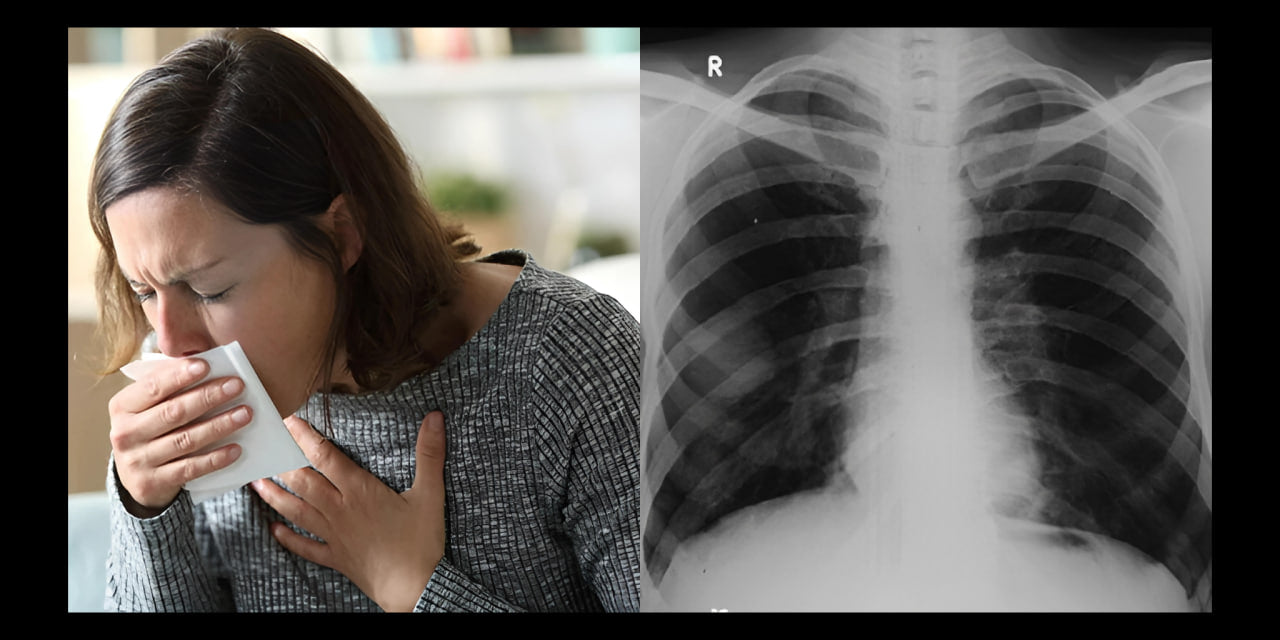

My name is Francesca van Vught, and for over four years, I suffered from coughing, breathing problems, and shortness of breath.

During this time, I visited several doctors and underwent the necessary tests. I repeatedly heard that my lungs looked good and I had nothing to worry about.

I am well aware that smoking cannot positively affect my symptoms. During my doctor visits, I was frequently told that smoking can lead to serious lung problems, including COPD (Chronic Obstructive Pulmonary Disease).

This progressive lung disease can permanently damage the airways, making breathing increasingly difficult.

Although my current symptoms did not directly indicate COPD, I was told that smoking is a risk factor I should not overlook.

Yet, no doctor had ever been able to tell me precisely where my symptoms stemmed from. COPD did not immediately emerge from the examination results as a possible cause.